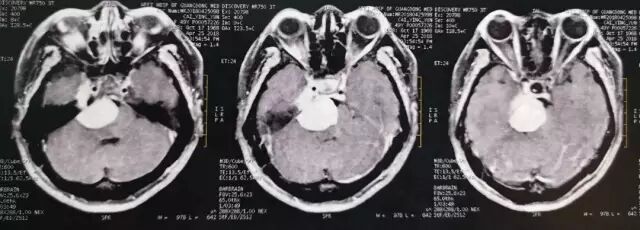

术后MRI T2加权像

术后MRI T1平扫,复查可见明胶海绵影(高信号)。

术后MRI增强核磁扫描